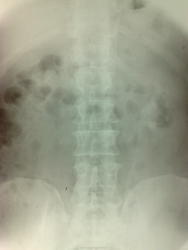

Не сильна в урографиях. Прошу помощи. Мужчина, 53 года. Левосторонняя попечная колика. УЗИ:  слева - каликопиелоэктазия, гиперэхогенные образования до 2 мм без акустической тени; справа - норма. Заключение микролиты левой почки. Чта скажете по данным снимкам? ОМП, 7минута, 14 и 21 стоя.

К сожалению, подрезан малый таз и что там, неизвестно ( , ЧЛС слева гипотонична, конкрементов вроде нет

А что за две округлые тени, которые выделяются на общем фоне. Слева

Если Вы имеете ввиду это, я бы назвала эти тени ортогональными проекциями чашек.

Вероятно, рентгеннегативные конкременты. С чашечками Вам виднее с размером - оригинал у Вас, есть и линейка.) Но я (на своё невооружённый взгляд) каликоэктазию бы не заключал. Тем паче лоханка нормальных размеров. Однозначно. Иначе, пиелоэктазия есть справа, как слева.)

На вертикальном снимке правую почку совсем потерял. Быстро очистилась... или нырнула совсем в малый таз.))